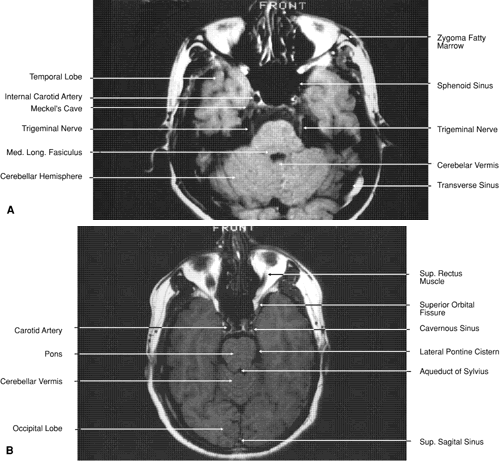

The globe is shown in Figure 12. The orbit and periorbital structures are shown in Figures 13 through 16, and the optic canal is shown in Figures 17 through 26. The cavernous sinus and optic chiasm are shown in Figures 27 and 28, and the posterior visual pathway and cranial nerves are shown in Figures 29 through 33.

Fig. 29. A. Axial computed tomography soft tissue image at the level of the base of skull. B. Axial computed tomography bone window image at the level of the base of skull.

Fig. 30. A. Axial T1-weighted image at the level of floor of orbit and trigeminal nerve. B. Axial T1-weighted image at the level of oculomotor nerve.